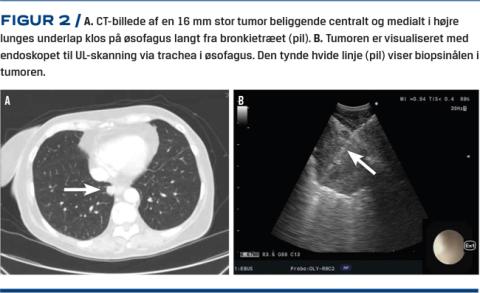

Med EUS-B-FNA kan man ud over at visualisere og bioptere lymfeknuder i mediastinum nå venstre binyre [2, 3], metastaser i venstre leverlap [4, 5], retroperitoneale lymfeknuder [5], lungetumorer [6] samt pleurale tumorer [7], og det er muligt at aspirere ascites- [8] og perikardievæske [9]. I Figur 1 ses en skematisk oversigt over strukturer, der kan biopteres ved hhv. EBUS-TBNA og EUS-B-FNA. I en randomiseret undersøgelse fandt man samme diagnostiske sensitivitet, når venstre binyre blev biopteret med enten det tyndere EBUS-endoskop eller det tykkere gastroenterologiske EUS-endoskop [3], men der mangler fortsat tilsvarende data for de øvrige nævnte strukturer. Ud over bioptisk at kunne verificere en eventuel spredning af en lungecancer og derved afværge en forgæves kurativt intenderet behandling er det en særlig styrke ved EUS-B, at man kan bioptere lungetumorer, der ikke kan nås fra luftvejene, men som ligger tæt på øsofagus [6]. På denne måde kan man undgå at udsætte patienten for en CT-vejledt perkutan lungebiopsi, der indebærer en langt større risiko for pneumothorax (Figur 2).